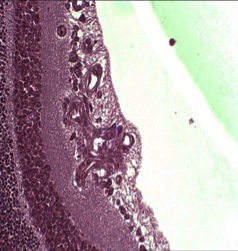

Ocular Histopathology and Immunohistochemistry

- GLP histopathology for ocular toxicology studies: ocular examination of globe and adenexal structures

- Histopathologic examination of ocular tissues from research studies

- Ocular pharmacology models

- Ocular immunohistochemistry

Histology Images